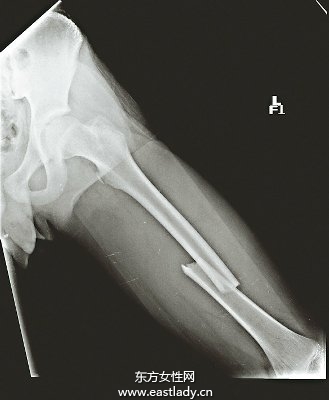

少年1年内二次大腿骨骨折 原因居然是...

少年1年内二次大腿骨骨折 原因居然是...,台湾一名14岁少年1年内二次大腿骨骨折,医师发现他骨质疏松提前来报到,有如老人家骨头,疑与他每天至少1罐可乐、不吃蔬果等不良饮食习惯有关。提醒民众注意骨质疏松不是老年人的专利,年轻人也不可轻忽骨质疏松的「隐形杀手」。